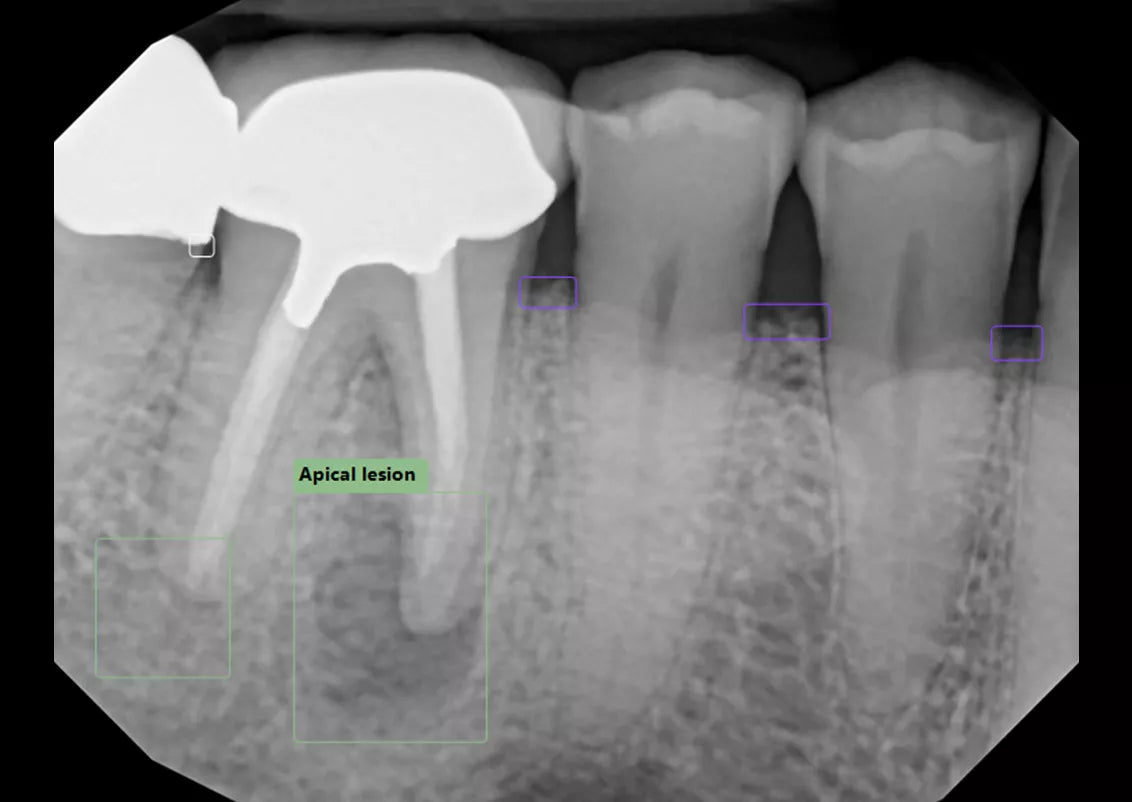

Built into DEXIS™ Imaging Suite Software, the DEXassist Solution provides assisted intelligence with a single click. This new solution enables users to identify up to six dental findings on 2D x-ray images.